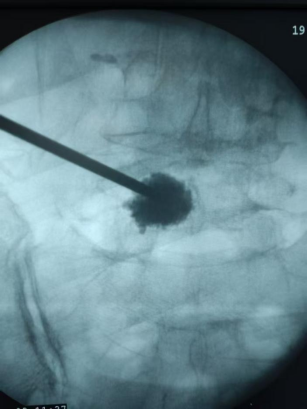

为尽快缓解李婆婆的疼痛,该院引进的高层次人才喻林博士为李婆婆完善了相关检查,在确诊李婆婆是腰椎骨折后,喻林博士为李婆婆量身制定了治疗方案,并为李婆婆实施了局麻下微创经皮椎体成型术,手术顺利,术后李婆婆腰骶部的疼痛立即得到缓解,可以佩戴支具下床进行活动,李婆婆对手术效果感到非常满意。

椎体成形术是通过向骨折的椎体内注入骨水泥,增强椎体的强度和稳定性,以达到迅速缓解疼痛,恢复椎体的正常功能的一种微创治疗手段。